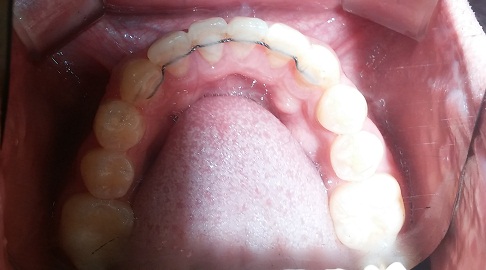

(27화 교정장치 제거 후 촬영, 아래에서 위로 찍은 사진)

(하악 안쪽 고정식 유지장치)

(상악 안쪽 고정식 유지장치)